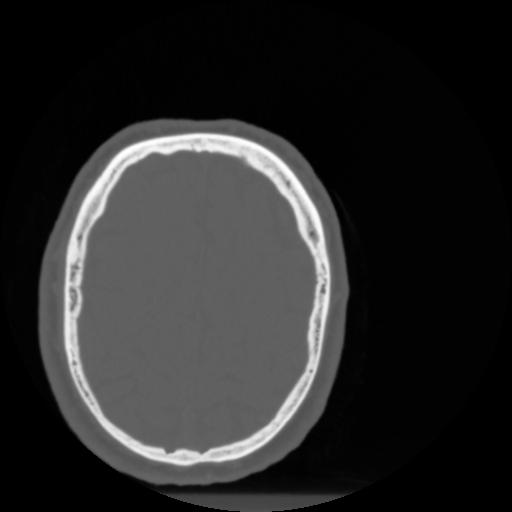

4 CEREBRO,,Vol,0.5,CEREBRO,,